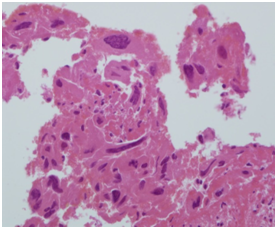

A specimen labeled as left frontoparietal hematoma - ? cavernoma from a 41 year old non-hypertensive female patient on ventilator was received for histopathologic examination. The patient was transferred from outside hospital to neurosurgical department of our hospital for craniotomy and evacuation of intracerebral hematoma. The clinoradiologic diagnosis was spontaneous intracerebral hematoma with intraventricular extension with normal ventricle, probably due to cavernoma. The microscopic examination of the specimen revealed extensive hemorrhage with peripherally placed mono-nucleated and multinucleated atypical cells. The mononucleotide cells were medium to large size with abundant cytoplasm and central large hyperchromatic nuclei. The multinucleated cells were large with abundant eosinophilic cytoplasm and hyperchromatic multinucleated bizarre nuclei. They were considered as cytotrophoblasts and syncytiotrophoblasts respectively (Figure 1-4). Immunohistochemistry showed that the atypical cells were CKAE1AE3 +, HCG+, GFAP-, CD31- and Vimentin- (Figure 5 to 10). A thin rim of GFAP positive glial tissue was seen in one fragment. Based on these findings, a diagnosis of metastatic choriocarcinoma was made. The patient survived the surgery and started recovering neurologically, but chose to go back to her own country for further management. So, we could not get any details of her obstetric history or previous medical illness.

Figure 2 Syncytiotophoblasts.

Figure 4 Syncytiotophoblasts.